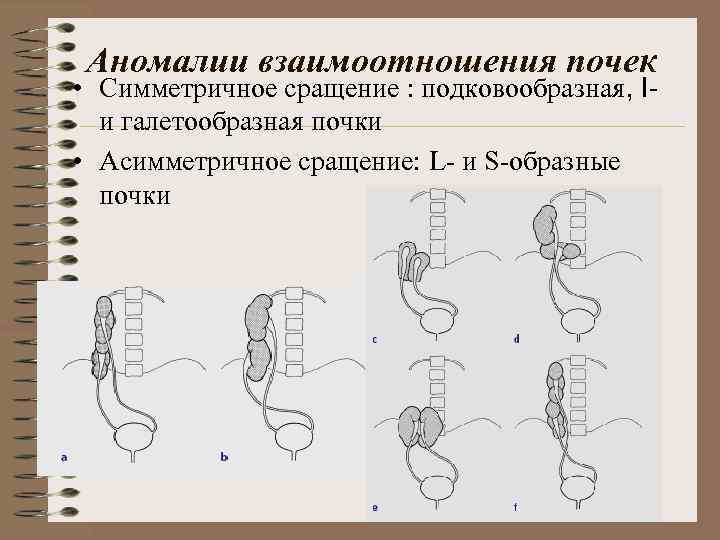

Аномалии взаимоотношения почек • Симметричное сращение : подковообразная, Iи галетообразная почки • Асимметричное сращение: L- и S-образные почки